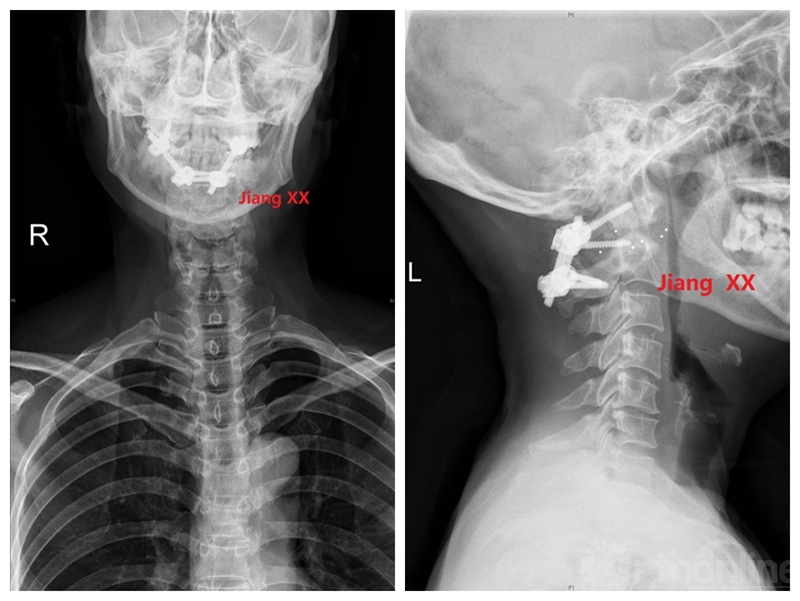

术后X线

病例二:患者女性,58岁,主因“颈部疼痛伴转头受限半年”入院,诊断为寰枢椎半脱位。

术前X线